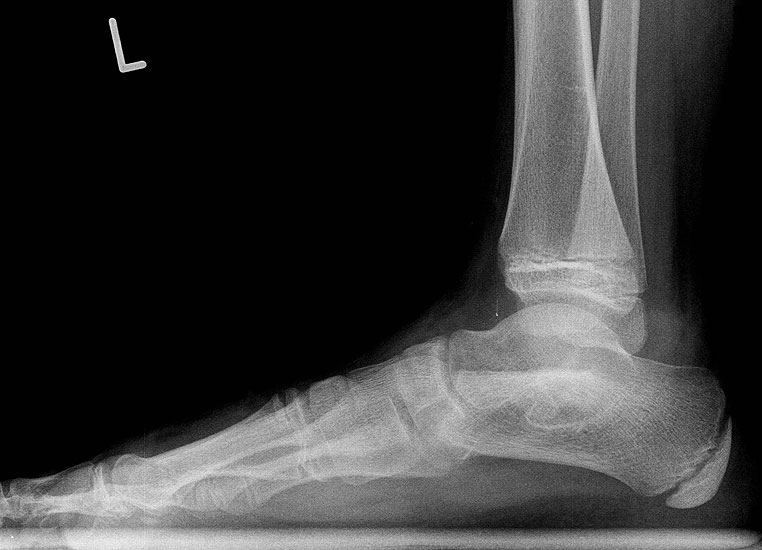

Die bildgebende Primärdiagnostik ist die Röntgen-Übersichtsaufnahme des Fußes im seitlichen, dorsoplantaren und schrägen Strahlengang. Weitere in der Literatur beschriebene Röntgen-Spezialeinstellungen sind durch die modernen dreidimensionalen Verfahren überholt.

In der Bildgebung ist bei dieser Form häufig eine einfache Röntgenschrägaufnahme (Abb. 8) ausreichend. Kombinationen mit talocalcanearer Coalitio werden beobachtet und sollten im Verdachtsfall ausgeschlossen werden. Für die Therapie wesentlich ist im Jugendlichen- und Erwachsenen-Alter das Ausmaß der degenerativen Veränderungen im Bereich des Talonavicular-Gelenkes.

Diagnostisch sollte neben Röntgenübersichtsaufnahmen (indirekte radiologische Zeichen: Dorsaler Traktions-Osteophyt am Taluskopf, „talar beaking“; kontinuierliche Linie der Trochlea-tali-Kontur übergehend in die Sustentaculum-tali-Kontur, „C-Zeichen“ (Abb. 11) 10) immer die dreidimensionale Bildgebung eingesetzt werden. Das MRT (mit Kontrastmittel) kann die Struktur der Brückenbildung und z.B. die Qualität des Restgelenkes (Knorpel-Dicke) besonders gut abbilden; das Dünnschicht-CT zeigt die knöcherne Feinstruktur im Bereich der Coalitio und den oft sehr schrägen Spalt-Verlauf im Frontalschnitt dagegen häufig genauer. Meist findet sich die Überbrückung im Bereich der medialen Facette; die Schichten sollten jedoch bis weit nach dorsal beurteilt werden, da ansonsten dorsomediale Formen übersehen werden können. Rozansky et al 7 unterschieden fünf morphologische Typen auf der Basis von 3-D-CT-Rekonstruktionen. Allerdings ist eine prognostische Zuordnung bisher nicht möglich.